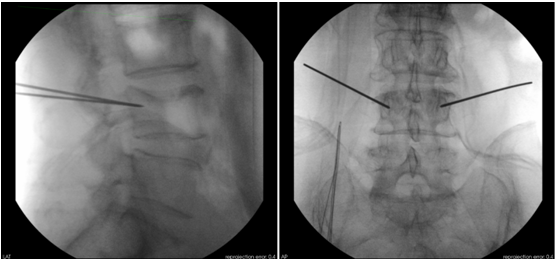

患者为70岁女性,腰部疼痛伴活动受限10天,在黑料网经MRI及CT检查示:腰4椎体压缩性骨折。经专家讨论后,医疗团队拟采用机器人辅助,局麻下行经皮球囊扩张椎体成形术。经过精密的仪器调试和配准,术前进行了反复的模型演练。刘时璋主任团队将患者的CT数据与机器人系统配准,工程师团队将事先规划好的个体化穿刺路径数据植入机器人系统。将术中的正侧位X线透视数据与CT数据融合后,机械臂按照术前规划路径,一次性穿刺成功,位置精准满意。

传统手术徒手穿刺需要在反复透视下,多次调整穿刺位置、方向及深度,增加了患者的不适感,且不一定能够达到理想的穿刺位置。而此例患者在脊柱机器人的辅助下,穿刺针精准地置入骨折塌陷位置,促使球囊扩张复位准确高效。穿刺过程中灵敏的压力反馈系统及可调的穿刺速度,大大增加了穿刺过程的安全性,使传统PKP手术更加精准、安全及高效,大大减少了术中透视次数及患者的不适感,同时为一些复杂骨折(如严重骨质疏松,骨性标识不明确;脊柱侧弯、旋转等)的个性化手术方案的实施提供了可能。前期,骨科病院也成功举办脊柱手术机器人培训会,团队认真学习并进一步认识到了骨科手术机器人良好的临床应用潜力,为此次手术的成功奠定了良好基础。